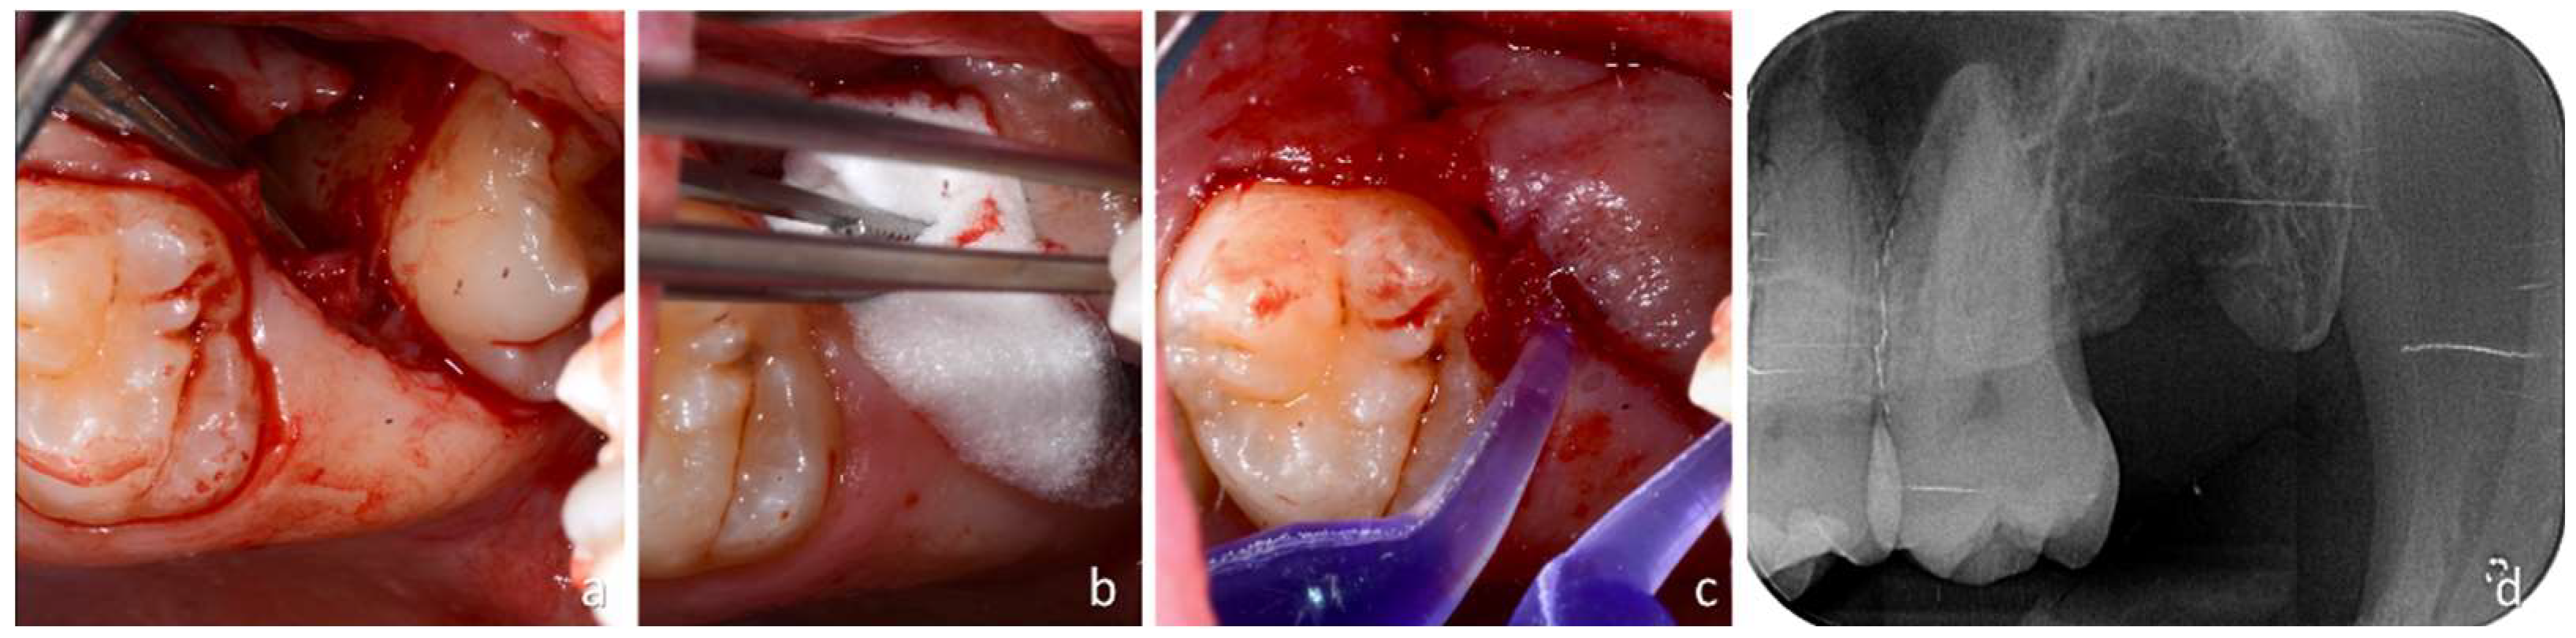

When, by gently moving the lever, it was deemed that the cementum-enamel junction of M3 had been reached, a rotation of the lever was started to push M3 out of the wound towards the oral cavity. Soft tissues were cut through an oblique incision, and the wound was spread apart by the emerging tooth during extraction (Figure 4a).

Subsequently, a revision of the alveolus was performed using a 3 mm Lucas bone curette to remove the follicle of M3 and possible thin bone walls that were fractured during the extraction of M3. Subsequently, a wash was performed with 5 mL sterile physiological solution directly inside the alveolus using a disposable syringe. An absorbable bovine collagen sponge (Hemocollagene, SEPTODONT; Rue du Pont de Creteil 94100, Saint Maur des Fosses, France) was inserted into the wound directly in the superficial portion of the socket to stabilize the clot (Figure 4b). As this surgical technique did not involve any flap lifting, the wound was closed using surgical glue (PeriAcryl® 90HV Cyanoacrylate Oral scription; GluStitch Inc. 307–7188 Progress Way—Delta, British Columbia V4G 1M6, Canada) directly on the wound (Figure 4c). A gentle stream of sterile saline solution was used to immediately set the glue, and an X-ray was taken to evaluate the complete extraction of the roots and possible complications, such as fractures of the tuberosity (Figure 4d).

Figure 4. (a) Dislocation of the wisdom tooth; (b) placement of a collagen sponge in the alveolus; (c) glue to fix the wound; (d) radiographic evaluation after extraction.